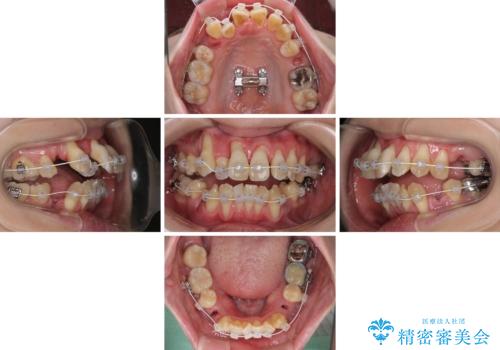

急速拡大装置 狭い骨幅を拡大した上で、顕著なデコボコを改善する抜歯矯正治療

上顎骨よりも下顎骨の幅が広く、更には下顎骨が左側に変位していたため、より良い咬み合わせを達成することを目的として、急速拡大装置を用いて上顎骨を拡大することとしました。

歯根露出が顕著であったため、歯の移動は早く、スムーズに治療を終えられるかと思いましたが、歯槽骨が硬く、治療は長期間に及びました。

過剰に力をかけ続ける事態となり、一部の歯では変色したり、神経が失活したりとトラブルが続きました。